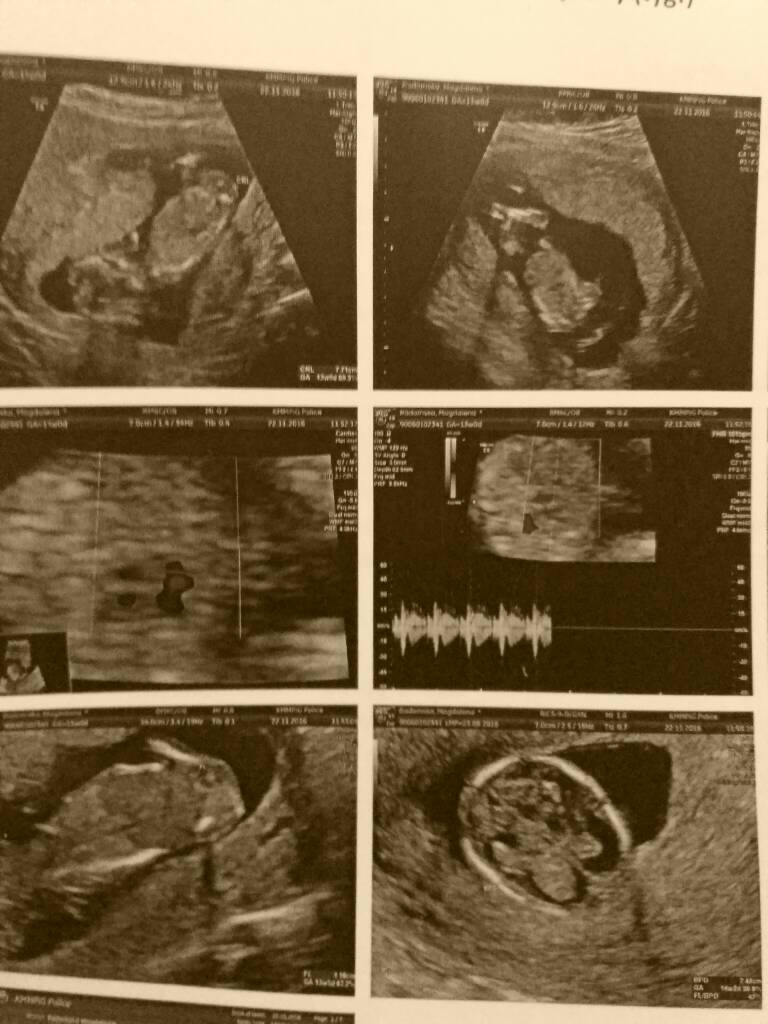

Super! Oby tak danej same dobre wieści były!Dziekuje dziewczynki za kciukijedno badanie za nami, z dzidzią wszystko w najlepszym porządku. Usg miałam w klinice Polickiej na patologii ciąży o i jeszcze nigdy nikt tak dokładnie mnie nie badał. Mały pozytywny szok

Zobacz załącznik 784366